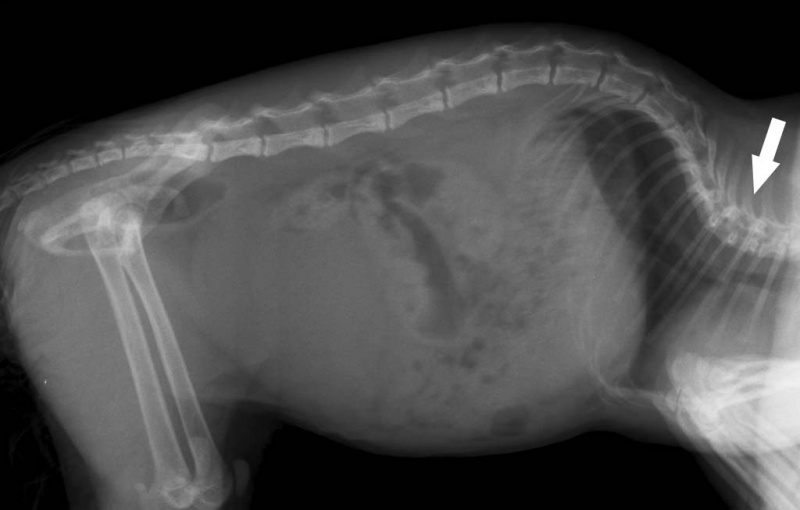

The characteristic and only genetic disease of short-footed cats is presented as lordosis of the vertebral part of the skeleton. With such a defect, pets can suffer stretching in the thoracic region. This pathology can also provoke additional diseases. Usually they concern the internal organs. The heart and lungs become the most vulnerable.

Lordosis

At risk are animals with different genetic abnormalities. Also, lordosis can hit a cat with obesity. For this reason, you need to carefully monitor the diet of the animal. It is strictly forbidden to overfeed him and deviate from the recommendations related to food.